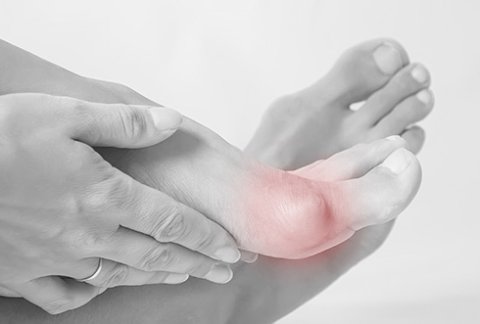

What is a bunion? Is surgery needed?

A bunion, medically known as hallux valgus, is a deformity characterised ...

Bunions or “a stone in my shoe”

Bunions are widespread in the population and definitely one of the ...